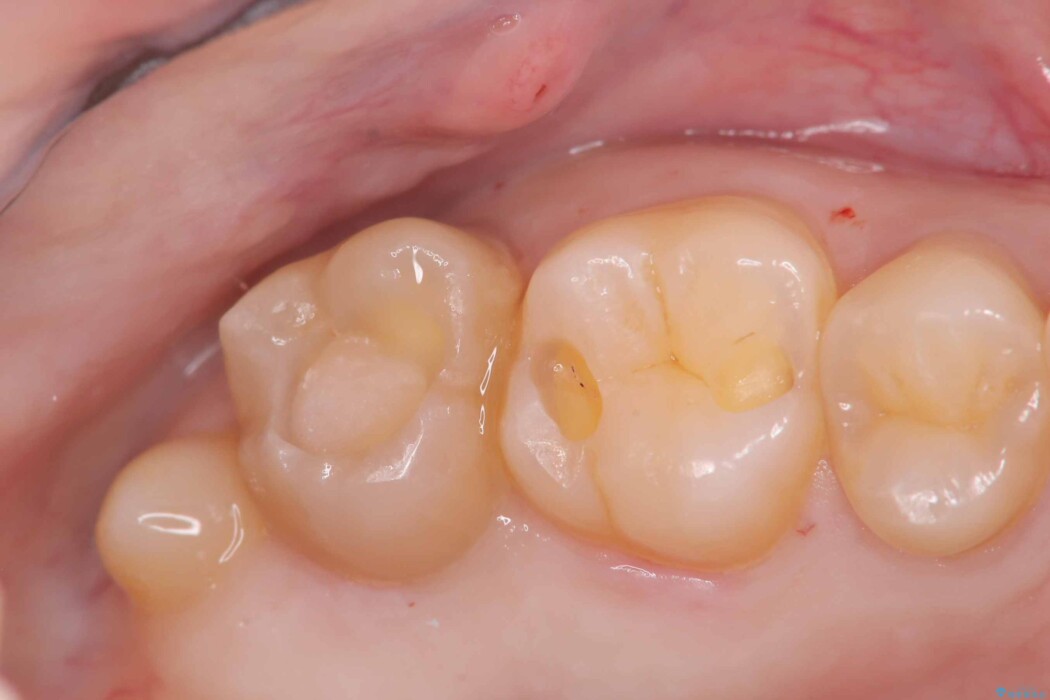

詰め物の下の見えない虫歯

以前に詰めた白い詰め物の内部で、虫歯の再発が確認されました。